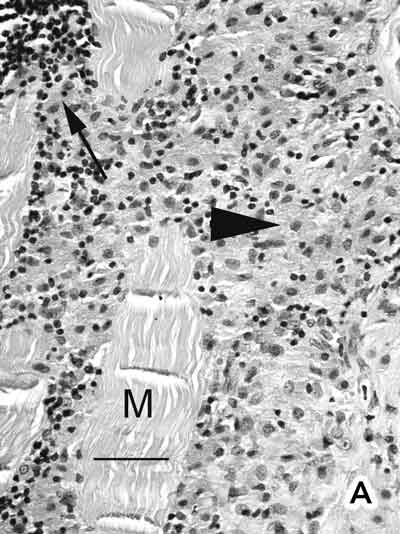

The interstitial connective tissue of the deltoid muscle contained a dense infiltrate of large macrophages (Figure A). Electron microscopy showed spiculated structures within these macrophages (Figure B). When an electron beam hits a sample it releases x-rays of wavelength specific to the elements in the sample. Using this principle, an EDAX x-ray detector revealed an aluminium peak (Kα, 1.48 keV) from the aggregates.

A: Deltoid muscle biopsy. Densely packed macrophages with abundant cytoplasm (arrowhead) were seen between muscle fibres (M), together with a few peripheral lymphocytes (thin arrow). No muscle fibre necrosis, regeneration, multinucleate giant cells, Michaelis–Guttmann bodies (found in malakoplakia) or granulomas were present. The macrophages stained positively with acid phosphatase and CD68. The lymphoid population showed a mixture of T and B lymphocytes. Stains for acid-fast bacilli were negative. (Haematoxylin and eosin. Bar = 50 m.) B: Electron micrograph showing electron-dense, randomly orientated, fine spiculated structures (asterisks) within a macrophage (M) (200 nm resin sections on nickel grids examined in a Philips CM120 electron microscope. Osmium and uranyl acetate. Bar = 1 µm.)